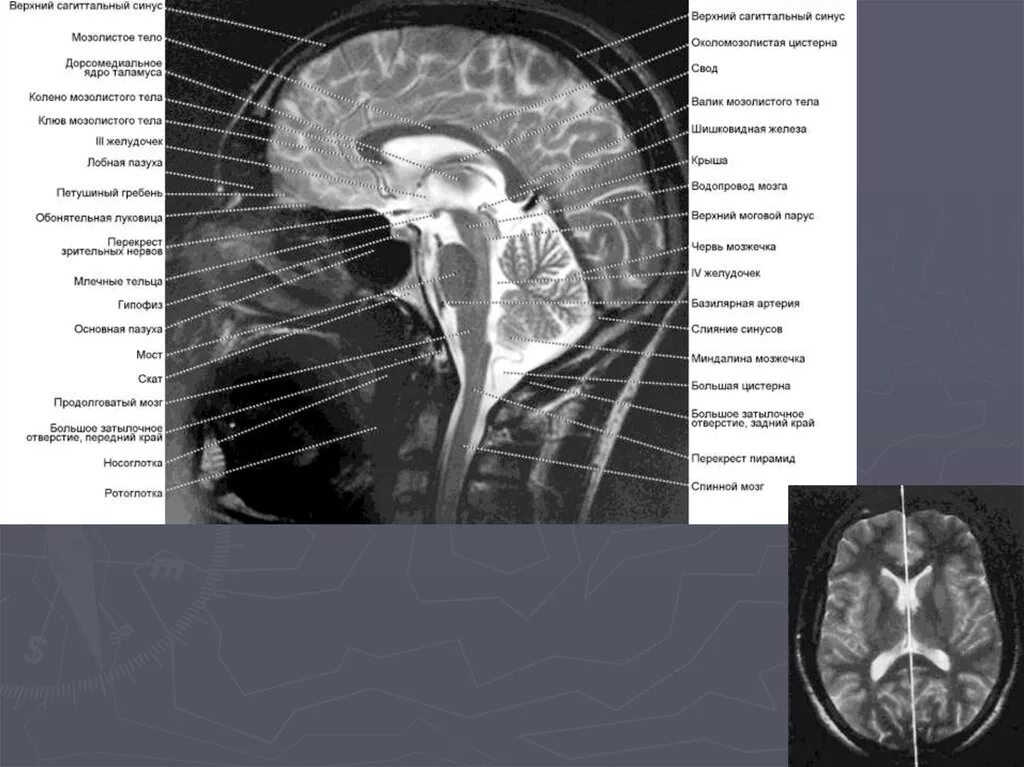

Цистерны на кт